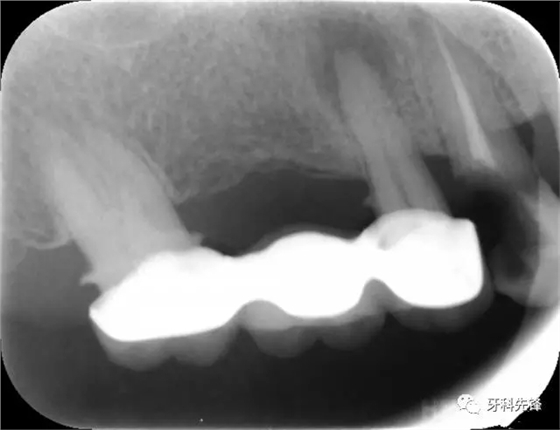

圖8治療術(shù)后X光片

640.webp (10).jpg

640.webp (11).jpg

640.webp (12).jpg